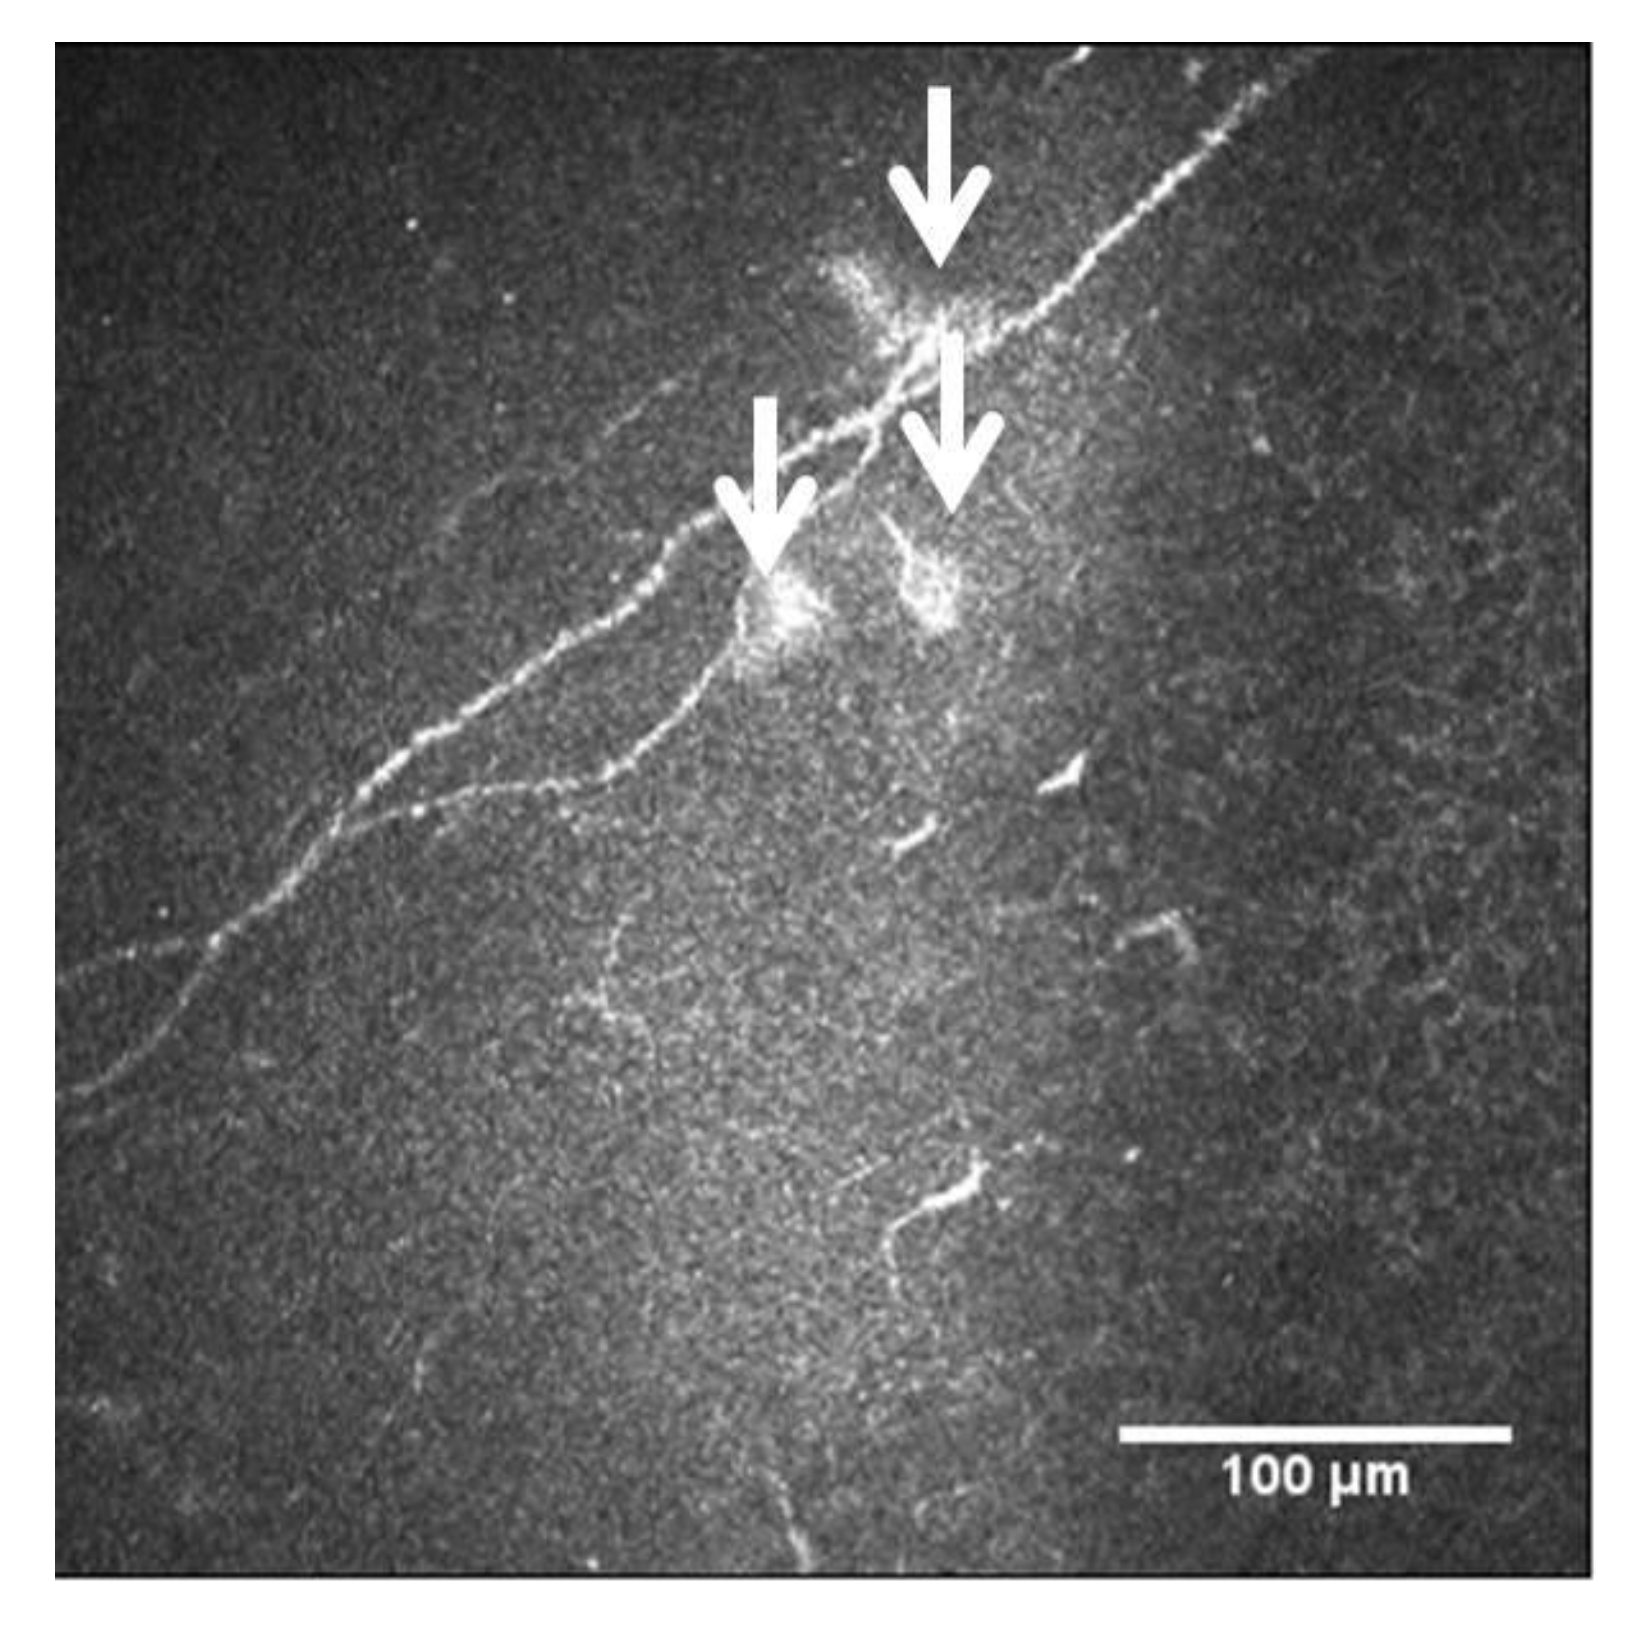

- Chinnery, H.R.; Rajan, R.; Jiao, H. Identification of presumed corneal neuromas and microneuromas using laser-scanning in vivo confocal microscopy: A systematic review. Br. J. Ophthalmol. 2022, 106, 765–771. [Google Scholar] [CrossRef] [PubMed]

3.1.2. Nerve Regeneration after Refractive Surgery

3.1.3. Ocular Surface Pathologies